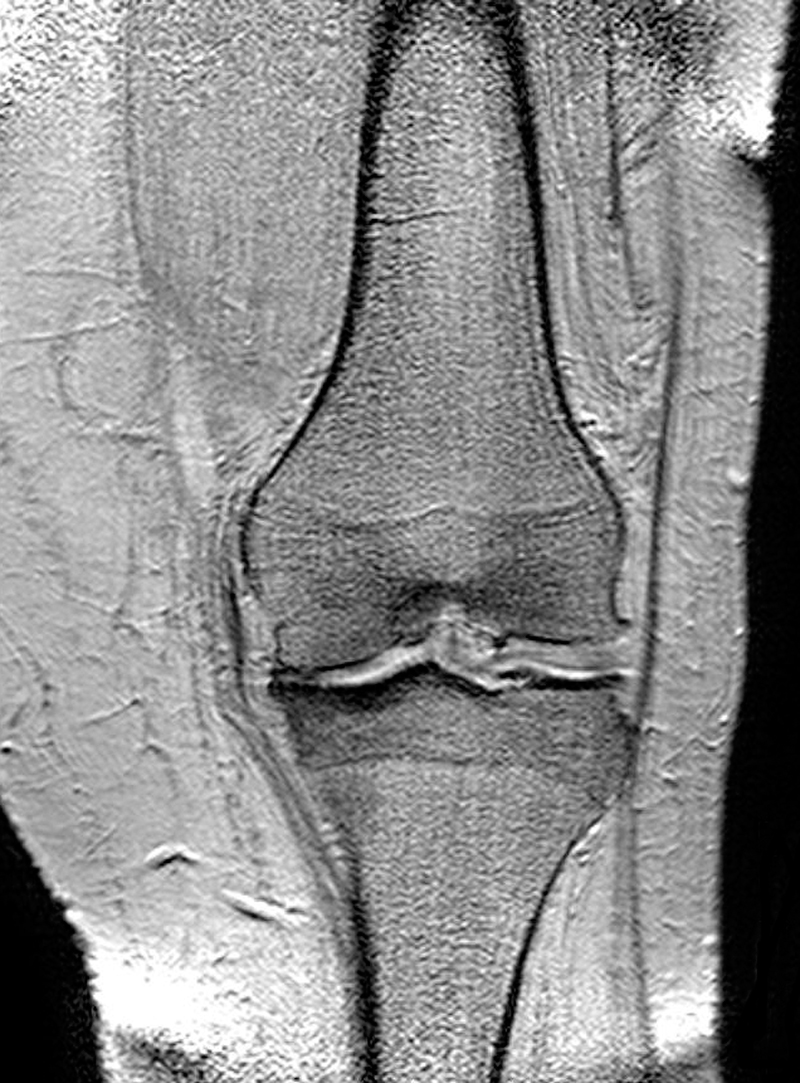

Arthrose ist weltweit die häufigste Gelenkerkrankung. In der Schweiz sind 20 Prozent der Bevölkerung über 60 Jahre betroffen. Die Krankheit führt zu Schmerzen, funktionellen Einschränkungen der Gelenke, verminderter körperlicher Aktivität und auch zu einem erhöhten Sterberisiko.